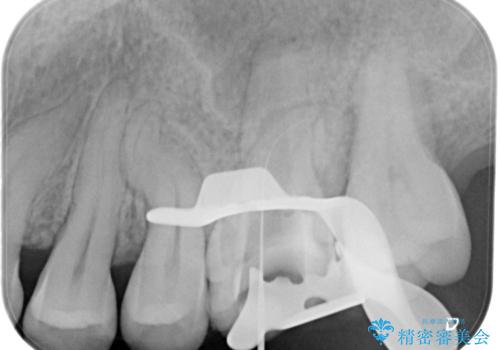

【見逃し根管を発見】根管治療〜セラミッククラウン

- 他院で根管治療した歯の再治療を希望されて来院されました。

未処置の根管があったため、マイクロスコープにて観察したことで、見逃しの根管を含めて清掃・充填を行うことができました。

上顎第一大臼歯は基本的に4根管です。